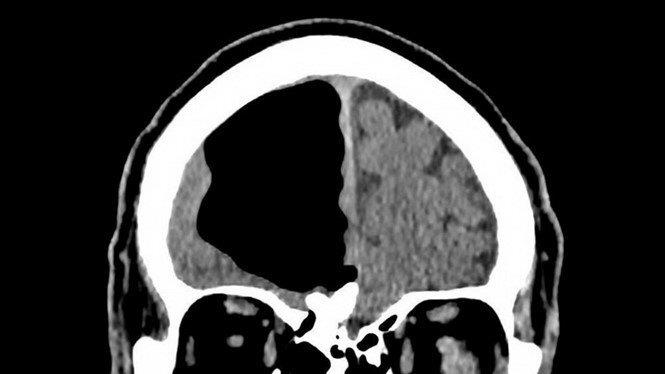

Cụ ông ở Bắc Ireland không khỏi choáng váng khi hay tin thùy não phải của mình hoàn toàn trống không.